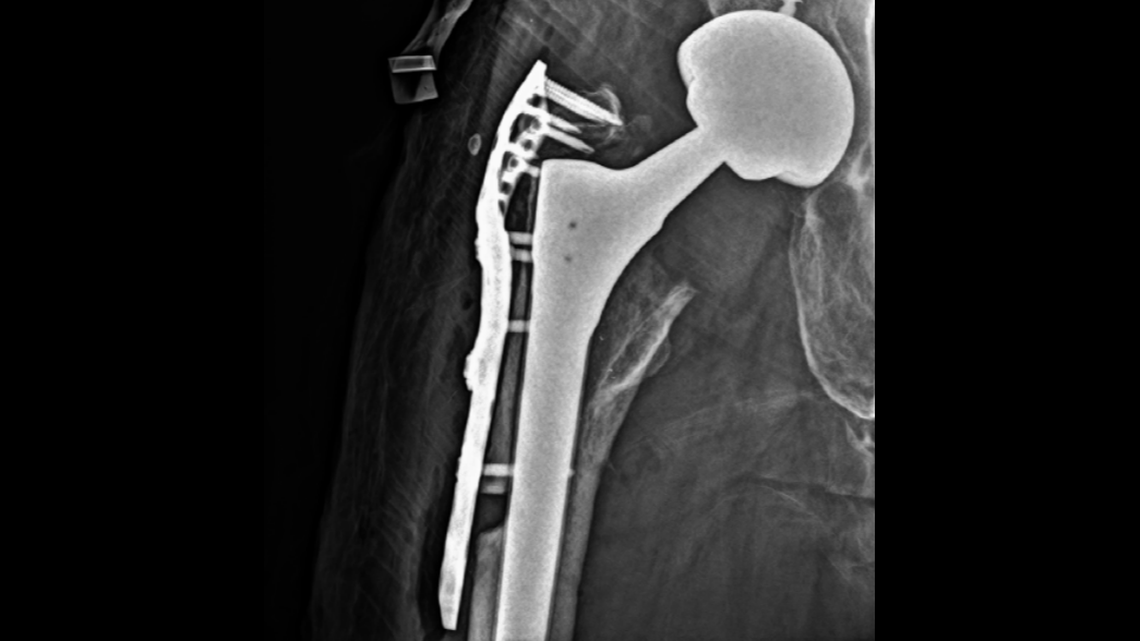

A new lawsuit filed in Maine shows x-rays from a woman’s follow-up surgeries after a hip replacement in 2019. The woman says her doctor cut away a piece of her femur and failed to close a gap of about 1 centimeter.

A new lawsuit filed in Maine shows x-rays from a woman’s follow-up surgeries after a hip replacement in 2019. The woman says her doctor cut away a piece of her femur and failed to close a gap of about 1 centimeter. Complaint

In June 2019, the doctor performed the revision surgery. He had to saw through her femur bone to remove the component, then knit the bone back together with wire, the suit says.

However, an x-ray shown in the suit shows a gap in Shea’s bone. She says once he cut through her femur bone, he failed to piece it back together and left a gap greater than 1 centimeter in her bone that couldn’t heal on its own.

Shea eventually switched doctors and got another surgery in December 2019 to add a stabilizing piece of hardware on her femur. The x-ray shows the new device and a gap in her femur bone that never healed.